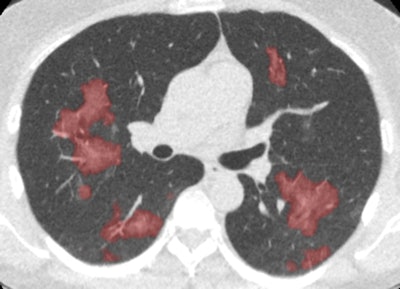

Based on the company's existing AI software for lung diseases, CAD4COVID-CT is designed for use with CT exams, while CAD4COVID-Xray is targeted at radiographs. CAD4COVID-CT assesses the suspicion of COVID-19, as well as the severity of the infection based on the percentage of the affected lung, according to the vendor.

Developed in collaboration with Radboud University Medical Center in the Netherlands and the Fraunhofer Institute for Digital Medicine MEVIS in Germany, CAD4COVID-CT was trained and validated in over 500 CT scans and performs at the same level as a radiologist, Thirona said.